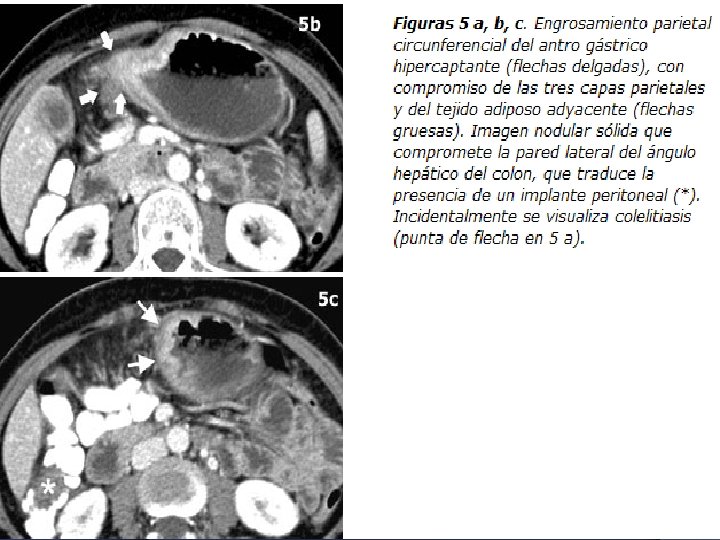

TAC: signos tomográficos